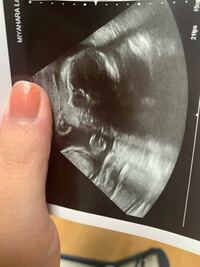

26w5d エコー写真 そうちゃん成長記録 ダウン症ボーイ

妊娠26週目 26w0d 6d のエコー写真とエピソード 妊娠7ヶ月 Cozre コズレ 子育てマガジン